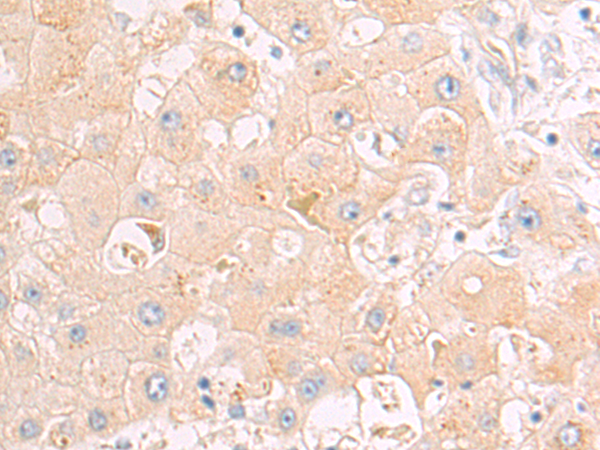

分类: 科研抗体货号: P00147别名: ANG3; ARP1; AngY; ANGPT3; UNQ162; dJ595C2.2应用: IHC反应种属: Human, Mouse